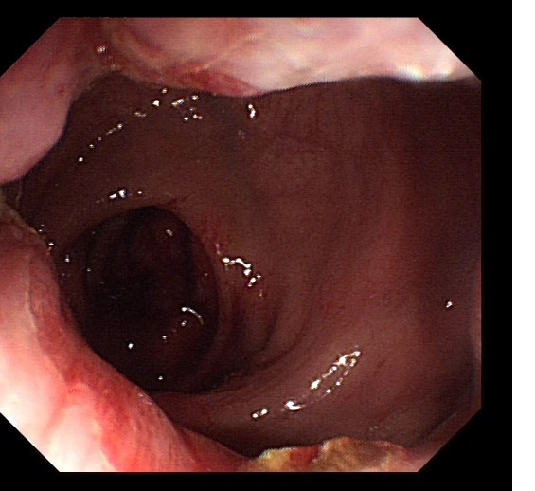

2018-12-12肠镜